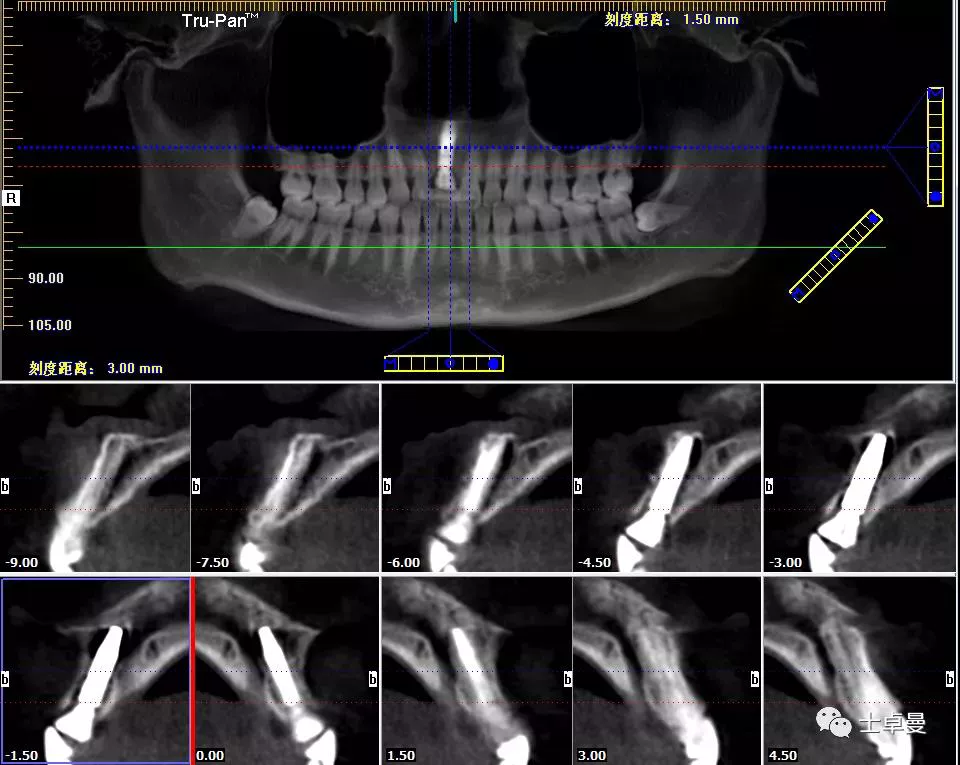

影像学检查,CBCT显示

· 11根管内充填致密,根尖未见明显阴影,根长约12mm;

· 唇侧牙槽骨完整,厚度约1.2mm;

· 根尖区剩余骨量约7mm。

术后即刻CT示,种植体植入位置理想